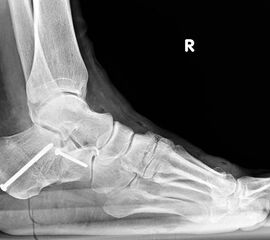

Konventionelles Röntgen

Stehende konventionelle Röntgenbilder eines Fußes mit Planovalgus Deformität Stadium II b dorsoplantar (dp) und seitlich. Auf der dp-Aufnahme zeigt sich die talo-calcaneare Divergenz, der gegenüber dem Kalkaneus nach anterior gleitende Talus und d

Stehende Aufnahmen des Fußes dorsoplantar (dp) und seitlich sowie des OSG anteroposterior (ap) sind die Grundlage der konventionellen Röntgendiagnostik (Abb. 5). Ergänzend werden gelegentlich die Rückfuβ-Alignement Aufnahme nach Saltzman 19 und Vergleichsaufnahmen der Gegenseite durchgeführt.

Der Talo-Metatarsale I Winkel bzw. die laterale talonaviculare Subluxation auf der stehenden dorsoplantaren Aufnahme des Fuβes dokumentieren das Ausmaβ des Vorfuβ abductus (Abb. 6 a,b). Ein dp Talo-Metatarsale I Winkel von > 10° (nach medial konvex) ist als pathologisch anzusehen. Mit der Bestimmung der talocalcanearen Divergenz (Abb. 6 c) erhält man ein Eindruck über das Ausmaβ des Rückfuβ valgus; eine leichte Divergenz bis ca. 12° gilt als physiologisch 20.

Auf der seitlichen, stehenden Aufnahme des Fußes wird ebenfalls der laterale Talo-Metatarsale I Winkel (Abb. 6 d) gemessen und so das kollabierte mediale Längsgewölbe dokumentiert. Auch hier gilt ein Talo-Metatarsale I Winkel von > 5° (nach plantar konvex) als pathologisch 21. Der Kollaps findet dabei meist im Talonaviculargelenk, seltener in der Naviculocuneiform-Gelenkreihe statt. Instabilität und Arthrose im 1. TMT sollten ausgeschlossen oder bei der Operationsplanung mit einbezogen werden. Weitere wichtige radiologische Messungen zur Beurteilung der Planovalgus-Statik und Progression der Deformität sind der laterale talo-calcaneare Winkel (Abb. 6 e) und der Abstand des Os cuneiforme-Unterrandes zum Untergrund (Abb. 6 f, Cuneiform height, 22. Eine anteriore Translation des Talus auf dem Kalkaneus findet man sowohl auf der ap, als auch auf der seitlichen Aufnahme des Fuβes mit Aufhebung der Cima-Linie.

Die stehende OSG ap -Aufnahme kann zunächst das fibulocalcaneare Impingement und im Endstadium laterale OSG Arthrose oder Valgus-Tilt des Talus zeigen.